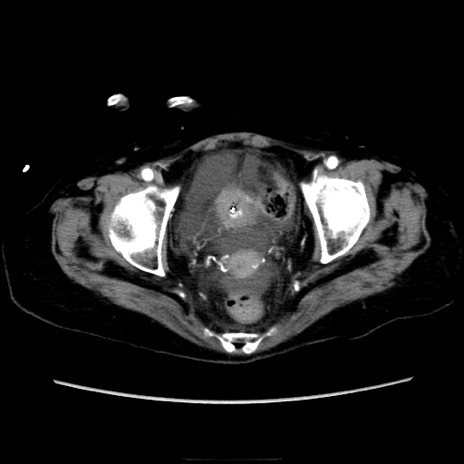

症例40(横断像)

【症例】90歳代女性

【主訴】腹痛・嘔吐

【現病歴】 食欲低下、嘔吐があり昨日他院受診。肺炎と診断され入院となる。入院後より腹部全体に圧痛あり。胃管留置され経過みていたが、症状持続するため、

当院転院となる。

【身体所見】腹部:中央に激痛あり、圧痛あり、反跳痛不明

【データ】WBC 17100、CRP 18.82

横断像